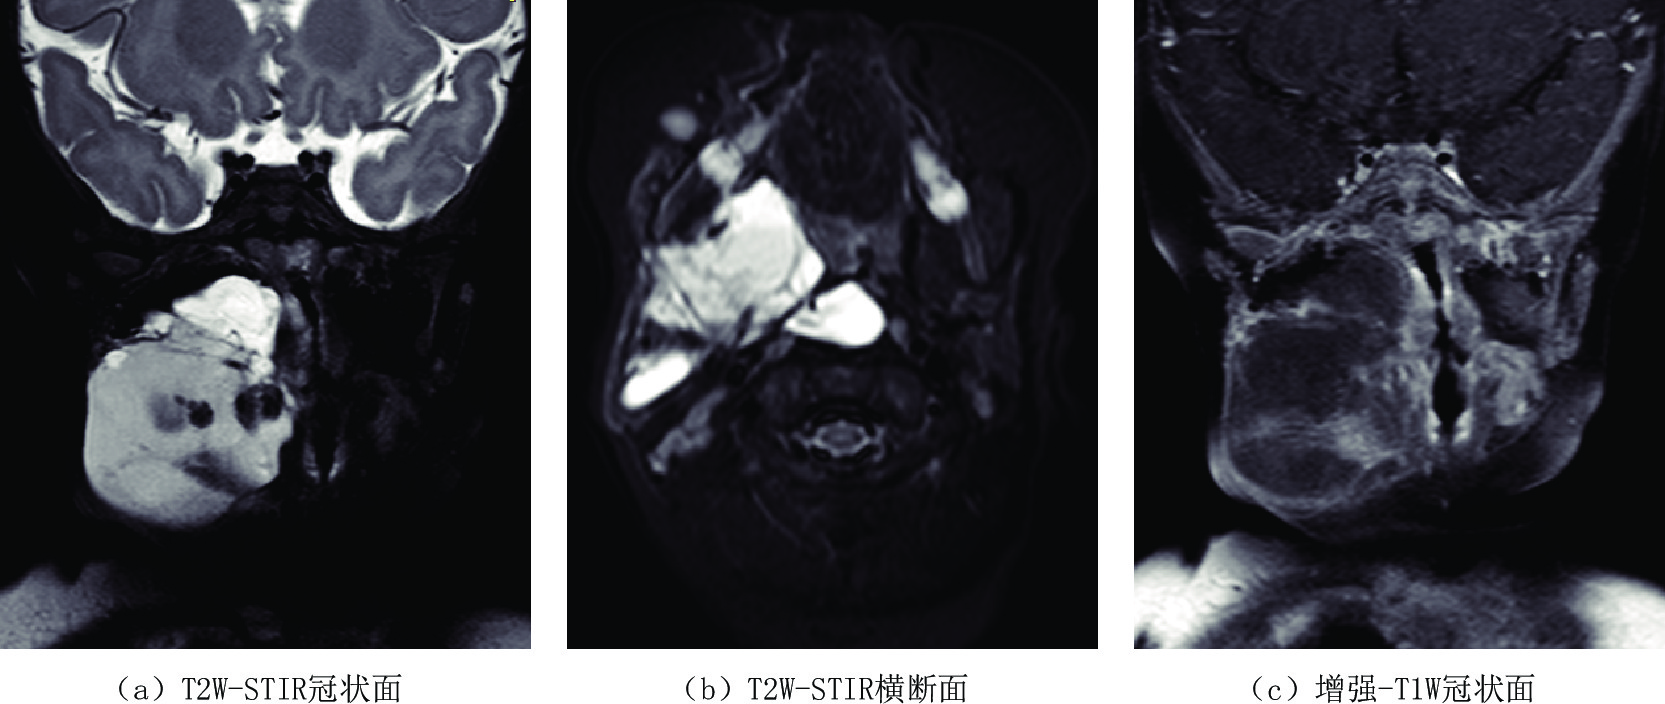

LMs多见于2岁以下的儿童,50% 的患者出生时即被诊断[19],但并不显著。随着患儿的生长发育解剖结构的逐步变大、淋巴液滞留的逐渐增多、异常淋巴管结构内的出血、感染以及创伤等因素,使得瘤体逐渐或突然增大,压迫邻近器官产生较严重的临床症状,如果发生在颈部淋巴管畸形可以压迫气道导致患儿呼吸困难[20](图5),CT/MR检查表现为囊腔张力增加,其内CT密度增高,MR检查则表现为T1 W信号不均匀增高或出现高低信号平面及T2W高信号,气道受压变窄。

![]() 图 5 女,5月,自幼右颈部肿物,近期增大。右侧口咽至下颌骨旁软组织内不规则囊性包块,T1W低信号T2W以高信号为伴等低信号,提示淋巴管瘤伴囊内出血,且口咽及喉咽部气道受压变窄移位Figure 5. Female, 5 months old recent enlargement of right neck tumor after birth. An irregular cystic mass with T1W low signal and T2W high signal with equal low signal in right oropharynx to paramandibular soft tissue, suggestive of lymphangioma with hemorrhage, as well as the compression of the oropharyngeal and hypopharyngeal airway

图 5 女,5月,自幼右颈部肿物,近期增大。右侧口咽至下颌骨旁软组织内不规则囊性包块,T1W低信号T2W以高信号为伴等低信号,提示淋巴管瘤伴囊内出血,且口咽及喉咽部气道受压变窄移位Figure 5. Female, 5 months old recent enlargement of right neck tumor after birth. An irregular cystic mass with T1W low signal and T2W high signal with equal low signal in right oropharynx to paramandibular soft tissue, suggestive of lymphangioma with hemorrhage, as well as the compression of the oropharyngeal and hypopharyngeal airway另外,肠系膜淋巴管畸形CT/MR检查表现为位于肠管间的囊性病变,CT增强检查可见肠系膜血管穿行其中(图6),可因剧烈活动或瘤体的重力作用牵拉肠系膜肠梗阻导致肠扭转、肠梗阻,或是外力撞击导致瘤体破裂、瘤体内出血等急症[21]。大网膜淋巴管瘤常因腹部无痛性逐渐增大而就诊,查体有波动感,在临床上需与大量腹水鉴别,影像学检查LMs表现为腹前壁下囊性病变将肠管推移,肠间隙变窄,而腹水一般聚集在低处及腹腔外围,含气肠管漂浮腹前壁下。

图 5 女,5月,自幼右颈部肿物,近期增大。右侧口咽至下颌骨旁软组织内不规则囊性包块,T1W低信号T2W以高信号为伴等低信号,提示淋巴管瘤伴囊内出血,且口咽及喉咽部气道受压变窄移位

Figure 5. Female, 5 months old recent enlargement of right neck tumor after birth. An irregular cystic mass with T1W low signal and T2W high signal with equal low signal in right oropharynx to paramandibular soft tissue, suggestive of lymphangioma with hemorrhage, as well as the compression of the oropharyngeal and hypopharyngeal airway